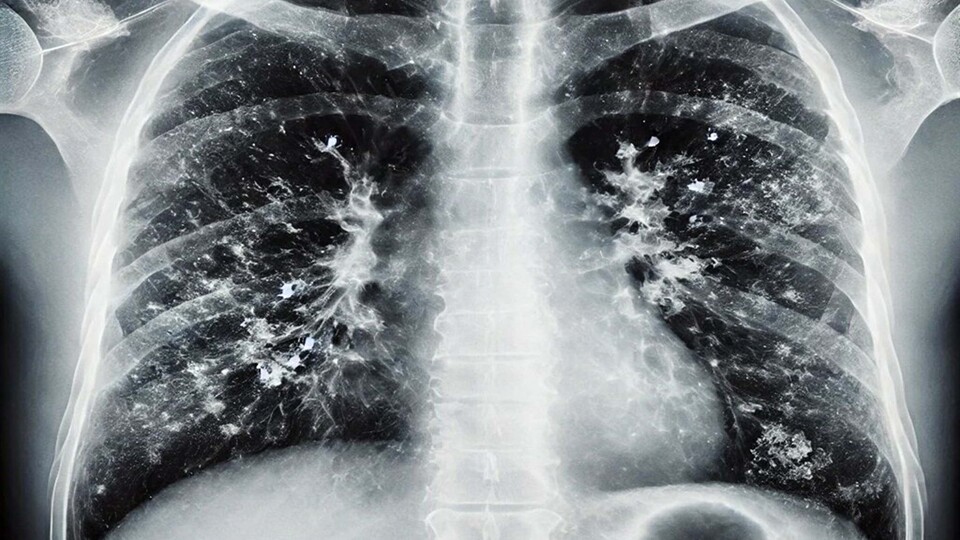

İzmir Katip Çelebi Üniversitesi Atatürk Eğitim ve Araştırma Hastanesi'nden Prof. Dr. Alper Şener, son dönemde viral enfeksiyonlarda artış yaşandığını belirtti. Gribal enfeksiyonlar açısından influenzada ciddi bir yükseliş olduğunu ifade eden Prof. Dr. Şener, "İnfluenza dışında RSV ve rinovirüs de görülüyor. Gribal enfeksiyon geçirdikten sonra bakteriyel enfeksiyonlar, süperenfeksiyon olarak ortaya çıkıyor. Bu süperenfeksiyonlar, bakteriyel olduğunda bazen ağır tablolara neden olabiliyor. Zatürre, pnömoni, akciğer iltihabı gibi durumlar hastaneye yatışa hatta oksijen desteği ihtiyacına sebep olabilecek klinik tablolara yol açabiliyor. Bu açıdan dikkat etmek lazım. Aile hekimine başvurduğunuzda ücretsiz grip aşınızı olabilirsiniz" dedi.

Özellikle 65 yaş üstü vatandaşlara yönelik uyarılarda bulunan Prof. Dr. Şener, "Bu grupta RSV dediğimiz viral enfeksiyon önem taşıyor. RSV, akciğerde yaygın enflamatuar tabloya sebep oluyor. Bunun da aşısı var. Cebinizden ücret ödeyerek yaptırabileceğiniz bir aşı. Özellikle 75 yaş üstü bireylerin mutlaka olması gerekiyor. 65 yaş üstünden başlarsak viral enfeksiyonlar ağır seyrediyor. Koronavirüs döneminde bunlara alışkındık; pandemi sonrasında da ağır viral enfeksiyon tablolarıyla karşı karşıya kalmaya başladık. Ciddi solunum yetmezliği, ateş, üşüme ve titreme semptomları; acil servise başvuru ve oksijen desteğine rağmen toparlanamama gibi durumlar görüyoruz. Bu nedenle bu hastalar, bazen normal servise bazen de yoğun bakıma yatmak zorunda kalıyor. Bu hastalar maalesef bazen her türlü tedaviye rağmen akciğerdeki ağır enfeksiyonun yaygınlaşmasıyla ölüme kadar ilerleyebilen klinik tablolara sebep olabiliyorlar" diye konuştu.

Hastalığı ayakta geçirenlere yönelik de değerlendirmelerde bulunan Prof. Dr. Şener, "Hafif geçirseler bile akciğerlerdeki hasar ilerleyen dönemlerde KOAH ve astım gibi tablolara sebep olabiliyor. Sonrasında ömür boyu ilaç kullanmak zorunda kalıyorlar. Bu konu da önemli. Bir diğer tablo ise kalp hastalığı, hipertansiyon ve diyabeti olanlar. Bu kişiler de ağır klinik tablolar geçiriyor. Atlattıktan sonra bakteriyel enfeksiyonlar sık görülüyor. Viral enfeksiyonu hastanede atlattıktan sonra geçmeyen öksürük nöbetleri ve balgam yaşanıyor. Bundan sonra da zatürre dediğimiz tablolar oluşuyor. Bu durumda kesinlikle antibiyotik alınması lazım. 65 yaş üstü gruba mesaj gitmesi gerekirse; hafif bir gribal enfeksiyon geçirdikten sonra öksürük ve balgam devam ediyorsa, uzman doktora veya aile hekimine mutlaka görünmek gerekiyor. Belki de zatürre oldunuz ve farkında değilsiniz. Gerekli tetkiklerin yapılması ve antibiyotik başlanması lazım" dedi.